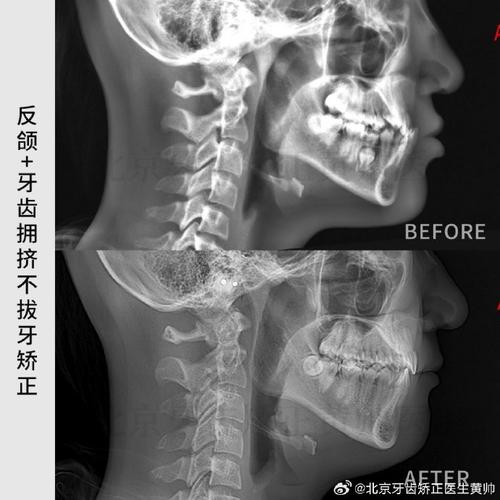

- ANB角:由上齿槽座点(A)、鼻根点(N)、下齿槽座点(B)构成,正常值2°±2°,是判断上下颌骨矢状关系的关键指标,ANB角>4°提示Ⅱ类骨性错颌(上颌前突或下颌后缩),<0°提示Ⅲ类骨性错颌(下颌前突或上颌后缩)。

正畸侧位片通过“77分析体系”的量化数据,可实现:①错颌畸形分类(骨性Ⅰ、Ⅱ、Ⅲ类,牙性深覆颌、深覆盖等);②制定个性化矫治方案(如拔牙与否、种植支抗设计、隐形矫治方案规划);③预测矫治后效果(通过计算机模拟分析骨骼、牙齿移动后的位置变化);④评估治疗后稳定性(对比治疗前后指标变化,防止复发),对于ANB角>4°的Ⅱ类错颌患者,若同时伴有U1-NA距过大,需设计上颌磨牙后移、切牙内收的方案;对于SN-Me角过大的垂直生长型患者,需避免使用垂直向牵引,以防面高进一步增加。